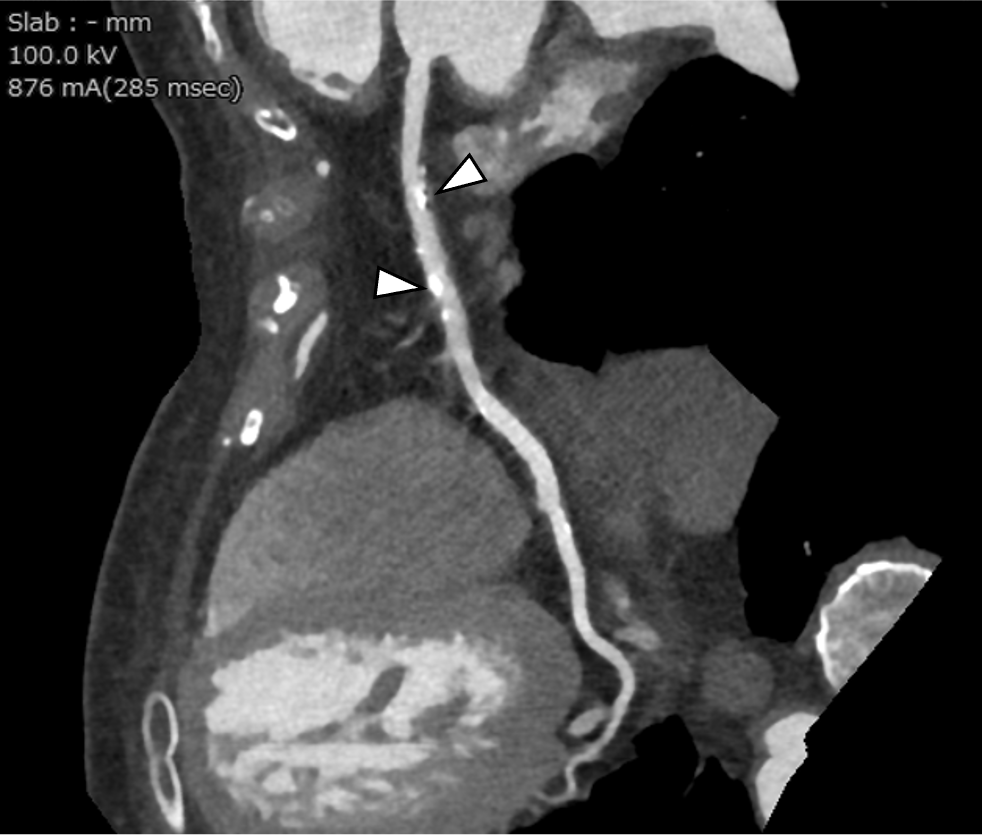

図3.angiographic view

RCA近位部~中間部とLAD近位部に石灰化がみられる(矢頭).

図5.curved multiplanar reconstruction(CPR)

RCAには石灰化プラークによる軽度狭窄がみられるが(矢頭),有意狭窄は認めない.